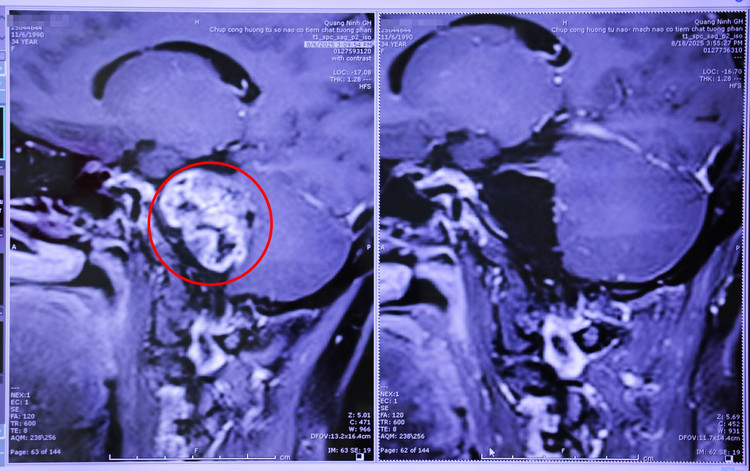

Trường hợp đầu tiên là bệnh nhân T.X.M (51 tuổi, xã Đầm Hà, tỉnh Quảng Ninh) ở nhà xuất hiện đau đầu, đau mặt do chèn ép dây thần kinh số V bên phải. Kết quả chụp MRI cho thấy, bệnh nhân M. có khối u màng não góc cầu tiểu não bên phải, kích thước 3x1,5cm, chèn ép cầu não, bọc quanh phức hợp thần kinh 7,8, chèn ép dây thần kinh số 5 và phức hợp thần kinh 9,10,11.

Bằng kinh nghiệm và sự hỗ trợ của kính vi phẫu, các bác sĩ ngoại thần kinh đã thực hiện phẫu thuật vi phẫu bóc tách thành công khối u màng não góc tiểu cầu phải cho bệnh nhân M, bảo tồn cấu trúc mạch máu thần kinh.

Hình ảnh chụp cộng hưởng từ khối u màng não góc cầu tiểu não phải được phẫu thuật lấy bỏ toàn bộ - Ảnh BVCC